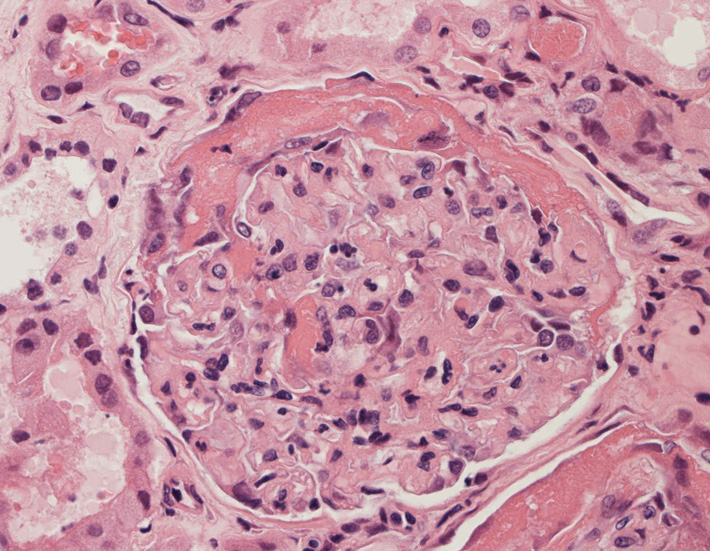

腎臓の病理組織所見-->壊死性糸球体腎炎

kidney01.jpg

kidney02.jpg

kidney03.jpg

Fig.01Fig.02Fig.03

kidney04pas.jpg

kidney05.jpg

kidney06.jpg

Fig.03(PAS)Fig.04(PAM染色)Fig.05(PAM染色)

kidney07.jpg

kidney08.jpg

Fig.06Fig.07 尿細管壊死